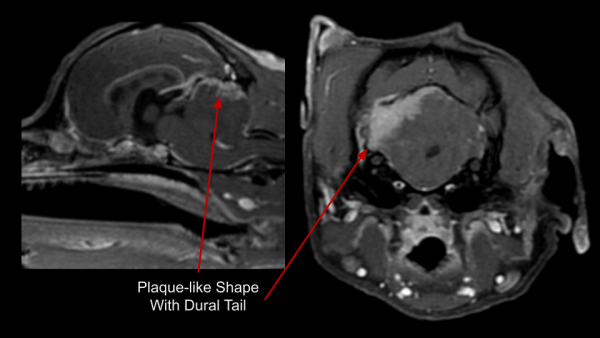

Meningiomas are typically benign and slow growing tumors arising from the meninges. They are commonly well encapsulated, focal, round, and solid. Less commonly, meningiomas can be invasive, have plaque-like shapes, or varied internal composition. They can occur anywhere along the CNS, but are most common around the brain. Meningiomas have a few key identifying characteristics; some or all may be present:

- Vivid contrast enhancement

- 'Dural Tail' sign

- Compression or herniation of other brain structures